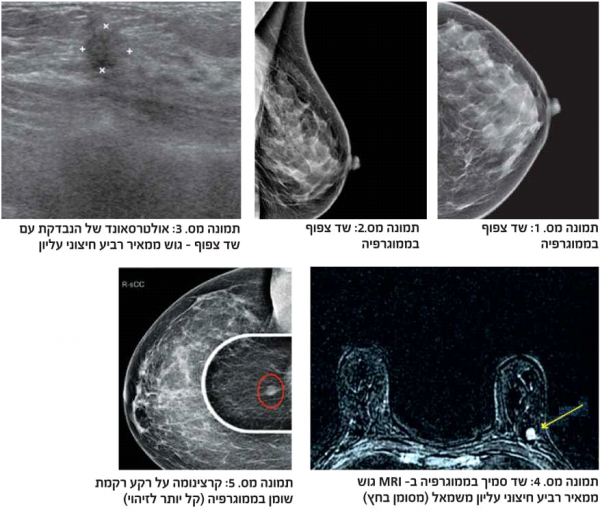

דוגמה לכך ניתן לראות בתמונות 1-4 בהן נראית רקמת שד צפופה (ללא גורמי סיכון נוספים), כפי שהיא משתקפת בממוגרפיה. בבדיקה זו לא נראה ממצא חשוד, אך בבדיקת האולטרסאונד נמצאה קרצינומה בגודל של 0.7 ס"מ (סנטימטר) בשד שמאל, ברביע החיצוני העליון. אותו ממצא נראה גם ב-MRI. לעומת זאת, תמונה מספר 5 היא דוגמה של בדיקת ממוגרפיה בה נראית קרצינומה על רקע של רקמת שד שומנית, עובדה המקלה על גילוי גידול מסוג זה.